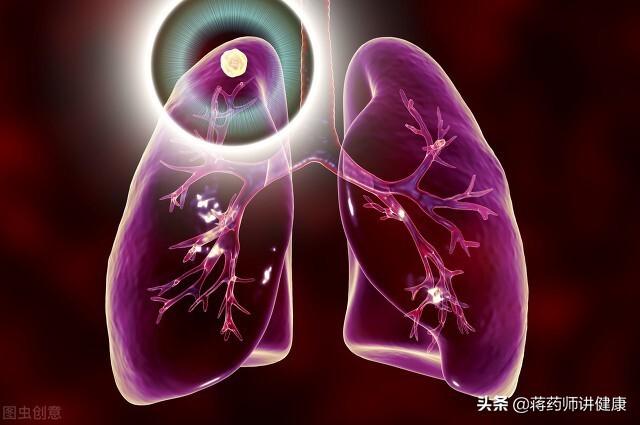

肺結節とは、胸部CTを撮影したときに映し出される肺の影を表す画像用語で、肺の中の多くの病気が肺結節を呈することがあります。

肺結節:肺の組織に現れる病変である。直径30mm以下の円形または不規則な病変で、正常な肺組織に囲まれていることが多い。医用画像では「肺の高密度陰影」と表現される。肺小結節は単結節または多結節で、境界が明瞭なものと不明瞭なものがある。

Qualitative:肺結節は、本人や家族では発見できない、あるいは発見しにくい異常で、病院で健康診断などの検査を受けたり、肺のCT、X線、MRiなどの検査をして初めて発見されることが多い身体的な異常です。

病変の数によって、肺結節は孤立性肺結節、多発性肺結節、びまん性肺結節に分類される。

結節密度の均一性によって、実質的な結節、純粋な挽きガラス結節、混合挽きガラス結節に分類される。

病理の種類によって、結節は良性肺結節と悪性肺結節に分類される。